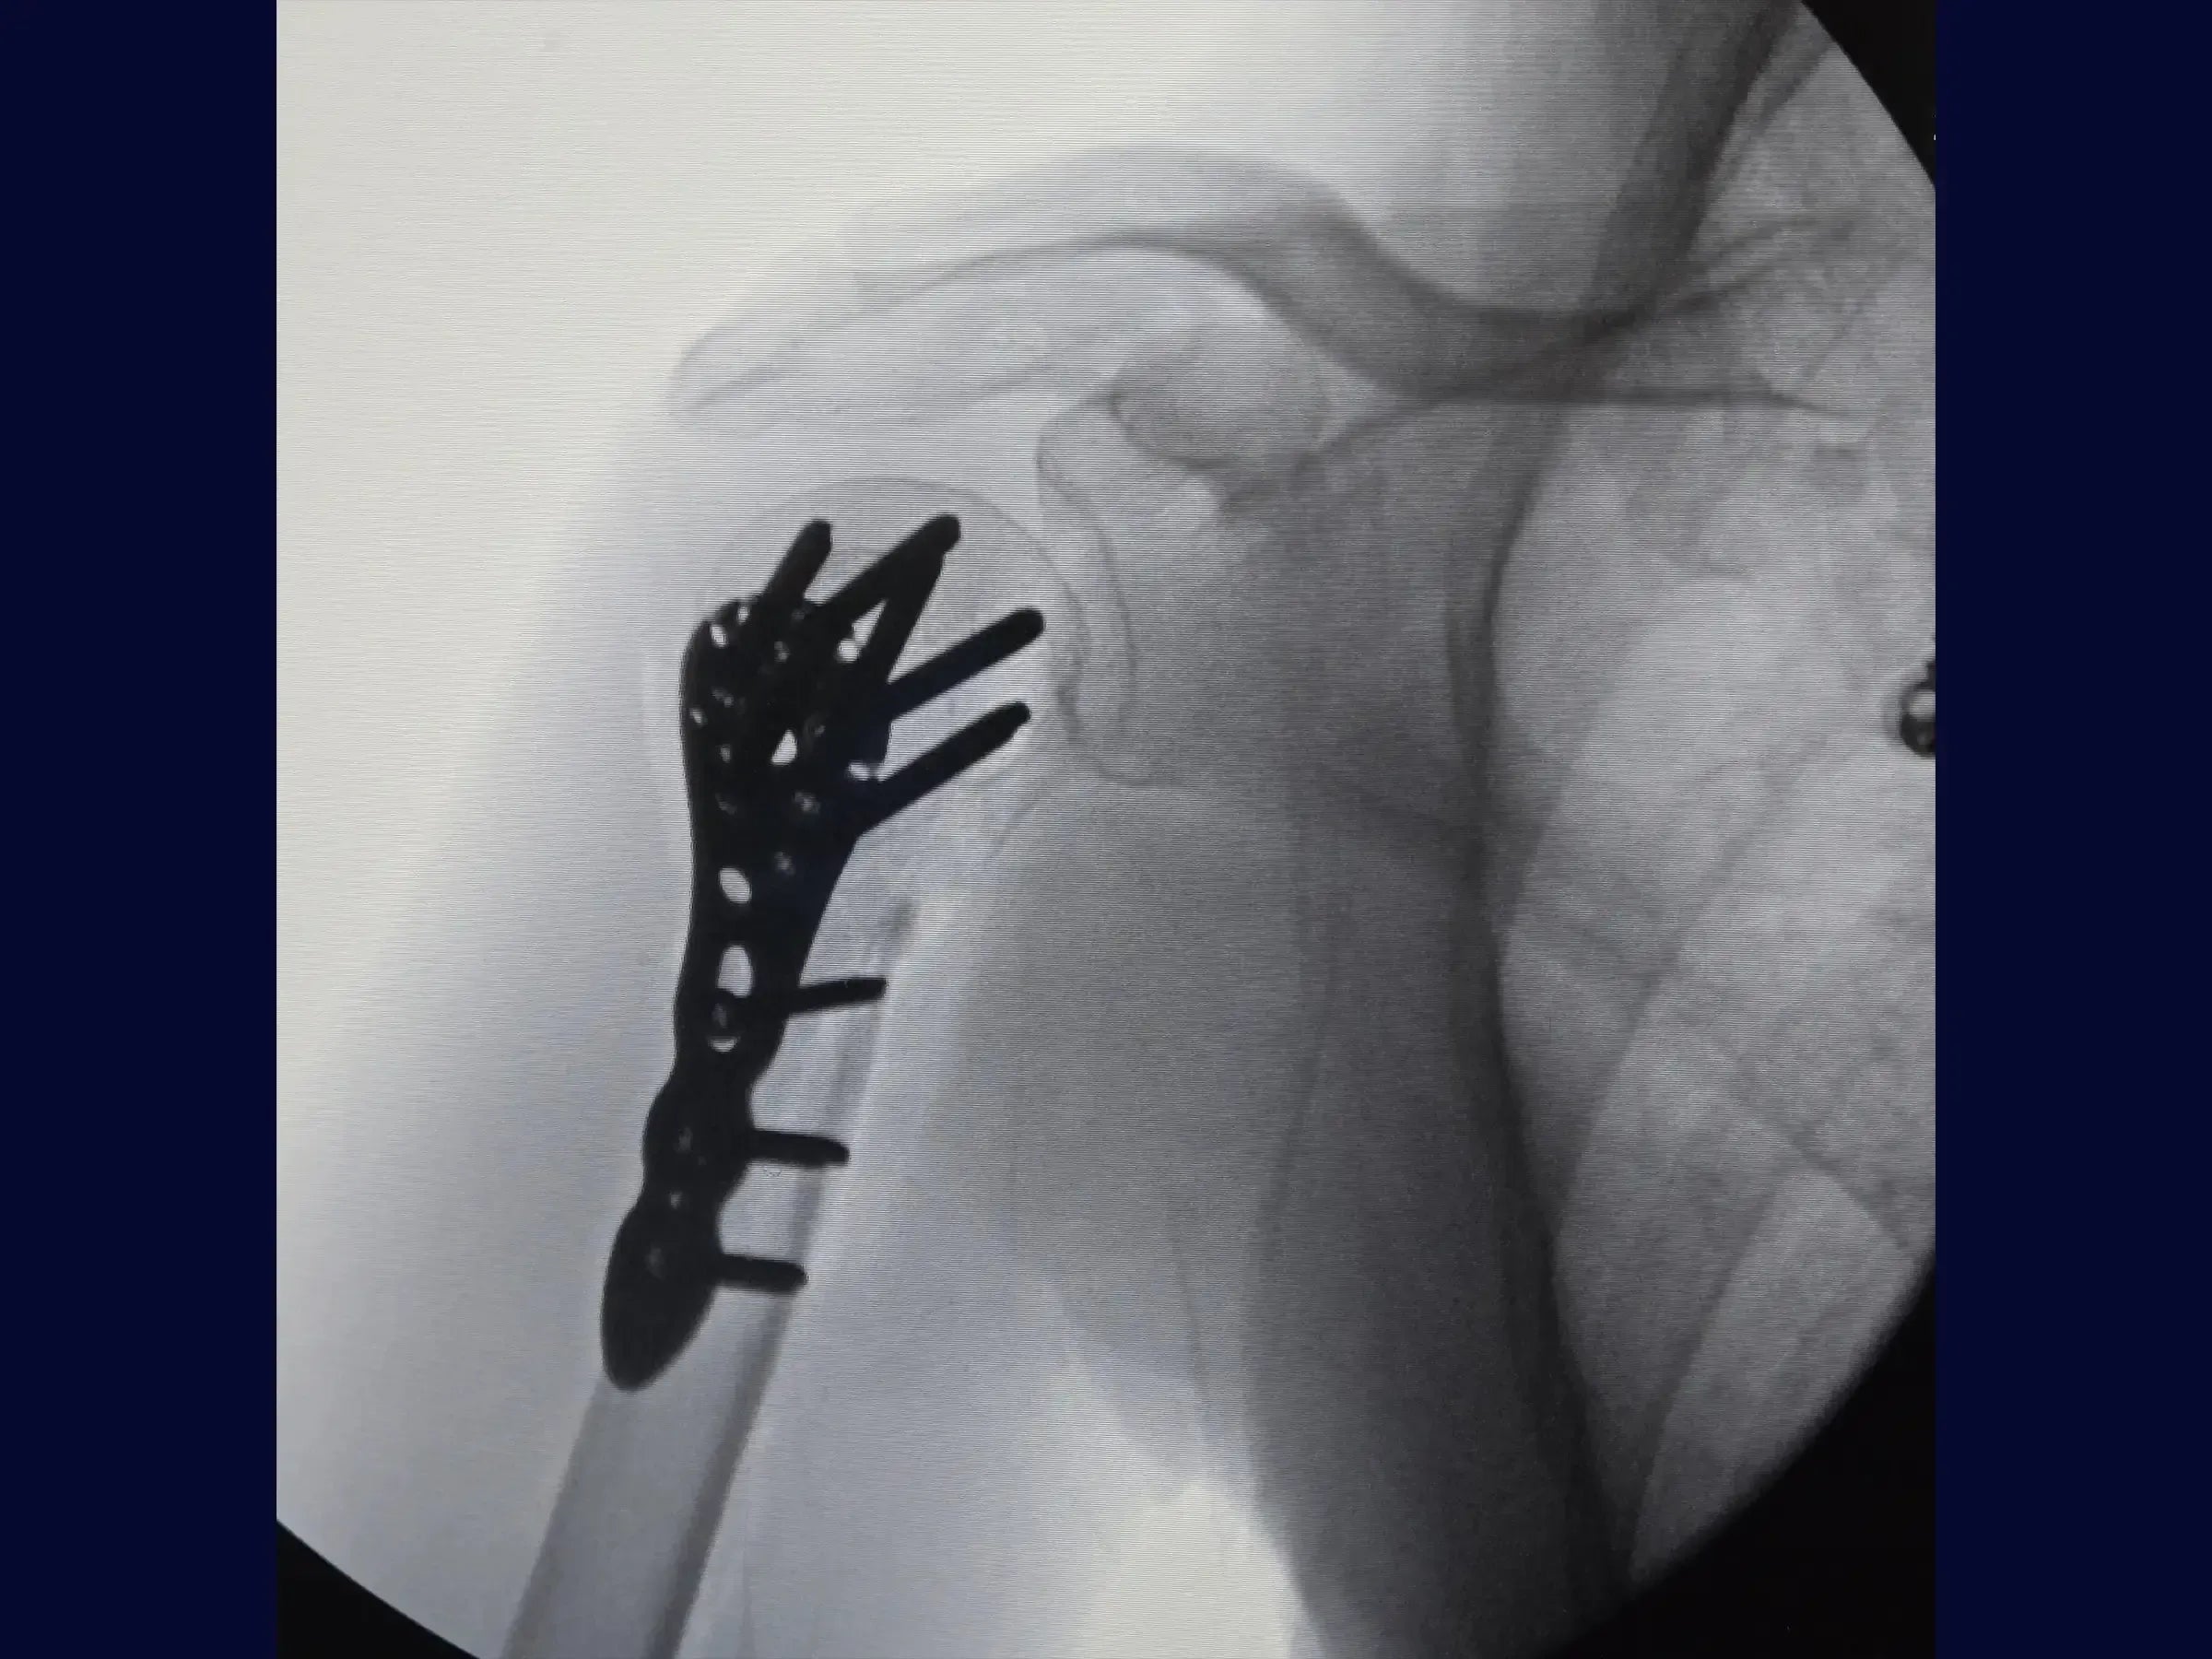

Proximal Humerus Fracture in 2 Parts (Deltopectoral Approach)

Master the treatment of proximal humerus fractures in 2 parts. This training offers a technical immersion in the deltopectoral approach for osteosynthesis, presented in 4K video from the surgeon's perspective, detailing each step of the procedure to optimize results.

- Anatomical reduction of proximal humerus fractures and provisional fixation.

- Brocage technique and measurement of screws for definitive subchondral fixation.

- Secure Subchondral Fixation: Drilling methodology with sensitivity for precise positioning of screws in the subchondral bone, without perforating the cartilage, with initial insertion of the screws from the calcaneus.